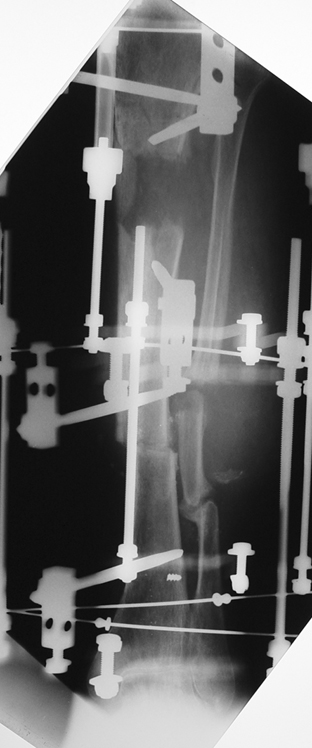

Appropriate radical debridement necessitates excision of all necrotic bone and soft tissues, and frequently causes instability at the involved extremity. The remaining bone and soft tissue defect has to be fixed and reconstructed. The distraction osteogenesis method of Ilizarov is used successfully for achievement of union, correction of the deformity, elimination of limb length inequality and reconstruction of segmental bone defects.

The duration of external fixation (external fixation index) depends on the amount of distraction required, and the extremity is prone to complications during this period. After the distraction phase is completed, the external fixator remains in place during the consolidation phase, which lasts twice as long as the distraction phase; but this period is hardly tolerated. If the external fixator is removed before sufficient consolidation is achieved, fractures, deformity and shortness will be the result. In our department, ‘lenghthening over nail’ method is used in order to decrease the external fixation index and increase patient comfort and activity level. In this method, the intramedullary nail is statically locked after the completion of the distraction phase, and external fixator is removed. The extremity is stabilized by the intramedullary nail during consolidation phase. In this way, complications due to long external fixation index or early removal of the external fixator are avoided.